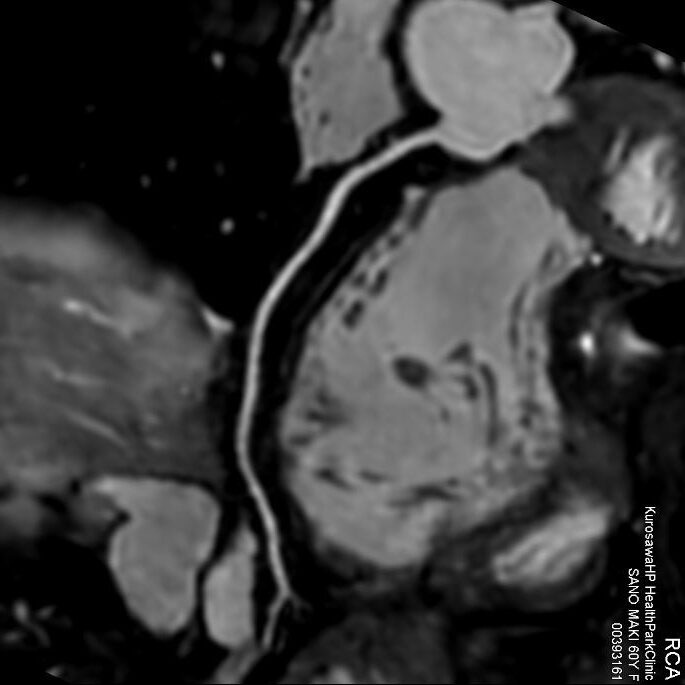

冠動脈MRA検査

『冠動脈CPR画像』

この検査は、被ばくもなく、造影剤を使わずに冠動脈を描出することができる画期的な診断方法です。

狭心症や心筋梗塞など、年々増えている「冠動脈疾患」。冠動脈MRA検査により、カテーテルによる冠動脈検査を行わずに冠動脈の狭いところを見つけること出来るようになり、心筋梗塞や突然死を未然に防ぐことに貢献しています。